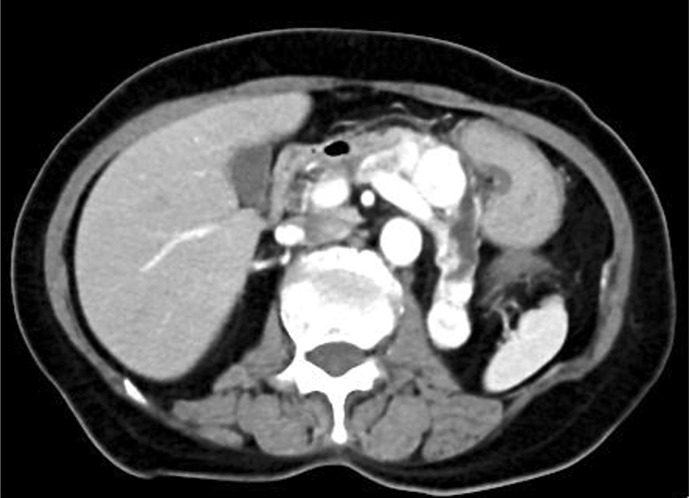

Case presentation: A 76-year-old woman who underwent radical nephrectomy for clear cell RCC (pT1bN0M0 Grade 3 INFb) at the age of 67 years presented to our hospital after her family doctor noted a pancreatic tumor. She was diagnosed with pancreatic metastasis of RCC based on histopathological examination, and avelumab and axitinib combination therapy was initiated. She developed irAEs, including myasthenia gravis, myositis, and myocarditis, which were treated with steroid pulse therapy. The patient recovered after treatment and was discharged without sequelae.